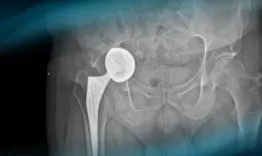

The goals of this clinical case are to discuss the different therapeutic options in case of acetabular loosening in total hip arthroplasty, to propose an innovative technique, and to see outcomes after revision hip surgery.

Management of an acetabular cup loosening with severe bone loss

Nicolas Reina, Nicolas Vari